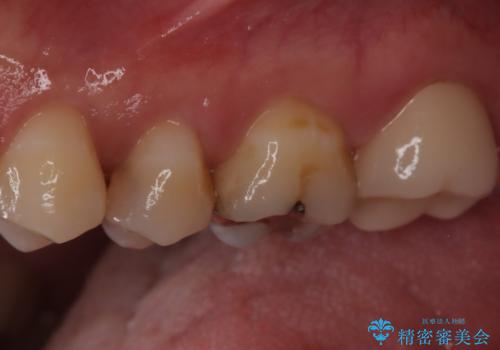

- 奥歯がズキズキ痛いことを主訴に来院されました。

治療にて歯髄は保存できないと判断したため、根管治療を行いセラミッククラウンにて修復しております。